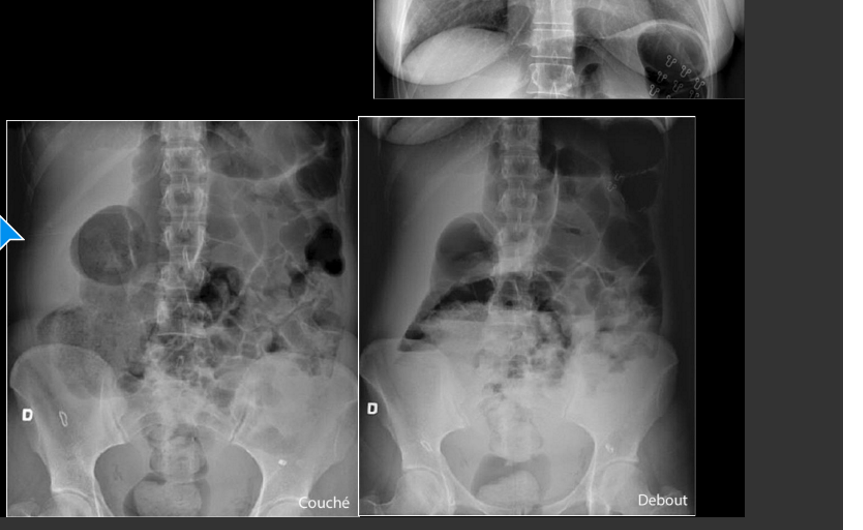

patho?

attention!!!

PNEUMOPÉRITOINE

ya de la marde en dessous qui represente surement illus paralytique en peritonte